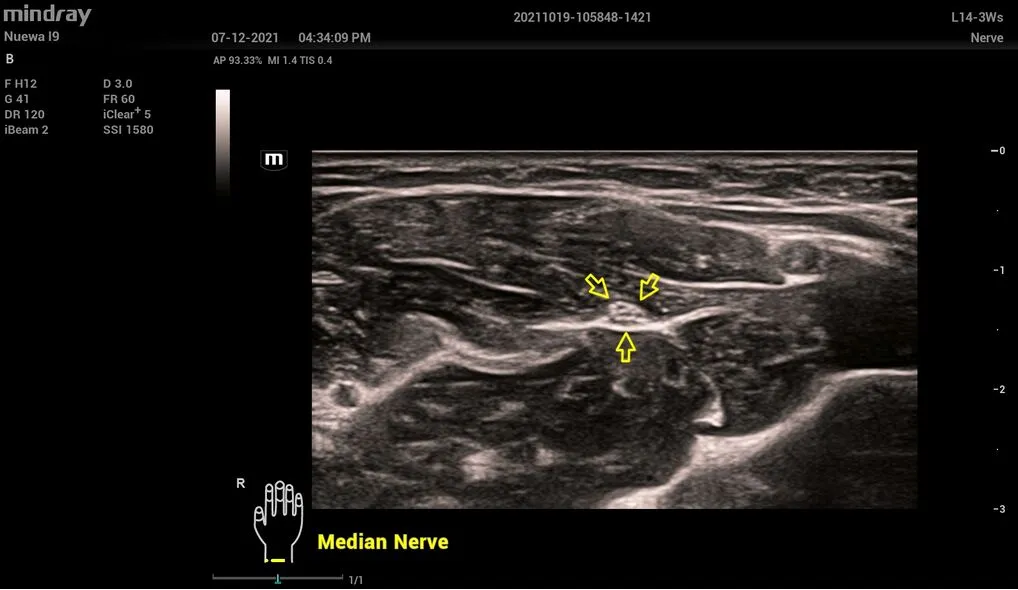

- L14-3Ws – линейный датчик для исследования сосудов, органов брюшной и грудной полости, педиатрии.

- L9-3s – линейный датчик для акушерства и педиатрии, исследования органов брюшной полости, опорно-двигательный аппарат, сосудов, нервов.

Средний нерв, L14-3Ws